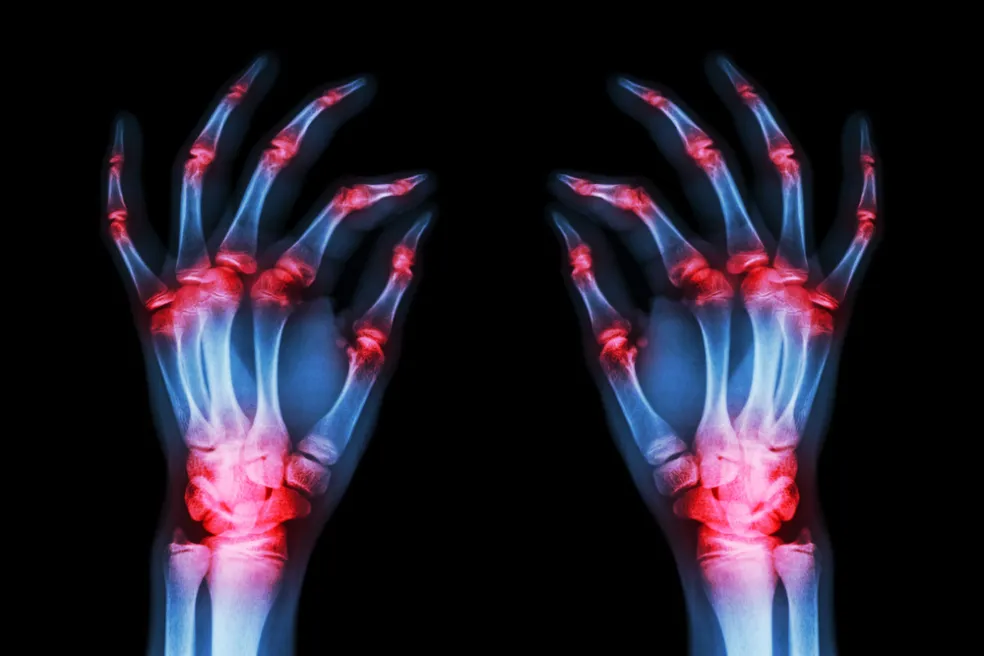

Jedným z najčastejších zápalových ochorení kĺbov je reumatoidná artritída, ktorá postihuje nielen kĺby, ale môže mať vplyv aj na ďalšie orgány. V tomto článku sa pozrieme na rizikové faktory, možnosti diagnostiky a liečby tohto ochorenia, ako aj na to, aký životný štýl môže pomôcť pri jeho manažovaní.

Reumatoidná artritída, ľudovo reuma, je zápalové ochorenie, ktoré patrí medzi najčastejšie typy artritídy (spolu s dnou, psoriatickou artritídou a mnohými inými diagnózami). Ide o autoimunitné ochorenie, pri ktorom imunitný systém omylom napáda zdravé tkanivá v tele, najmä kĺby. Tento zápal spôsobuje poškodenie kĺbových štruktúr a môže viesť k trvalému poškodeniu, ak sa ochorenie nelieči.

Postupne sa poškodzujú nielen kĺby, ale aj okolitá tkaniva, ako sú šľachy a väzy. Reumatoidná artritída môže zasiahnuť viacero kĺbov naraz, obvykle na oboch stranách tela. Okrem kĺbov môže zápal postihovať aj ďalšie orgány, ako sú srdce, pľúca či oči, čo robí toto ochorenie komplexným a zložitým na liečbu.

• bolesti a opuchy v kĺboch, najmä v rukách a nohách,

• deformácie a znížená pohyblivosť kĺbov,

Na potvrdenie diagnózy sa často využívajú aj zobrazovacie techniky, ako röntgenové snímky a ultrazvuk. Röntgen môže ukázať poškodenie kĺbov, ako sú erózie kostí alebo zúženie kĺbových priestorov, zatiaľ čo ultrazvuk pomáha odhaliť zápal v kĺboch ešte pred viditeľnými poškodením. Kombinácia týchto vyšetrení je kľúčová pre stanovenie presnej diagnózy a výber optimálnej liečby.